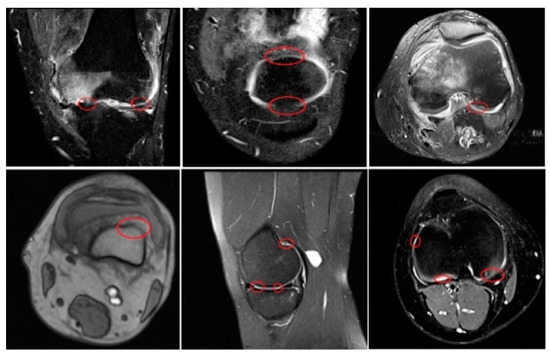

1. Introduction

2. Recent Methods of Cartilage Segmentation

3. Materials and Methods